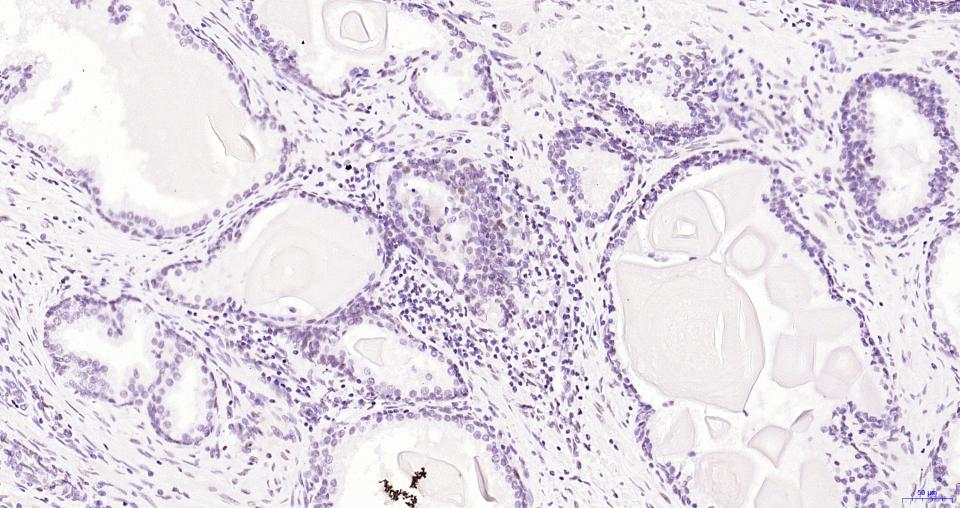

Paraformaldehyde-fixed, paraffin embedded Human Prostate; Antigen retrieval by boiling in sodium citrate buffer (pH6.0) for 15 min; Antibody incubation with BRD4 Monoclonal Antibody, Unconjugated(bsm-61190R) at 1:200 overnight at 4°C, followed by conjugation to the bs-0295G-HRP and DAB (C-0010) staining.